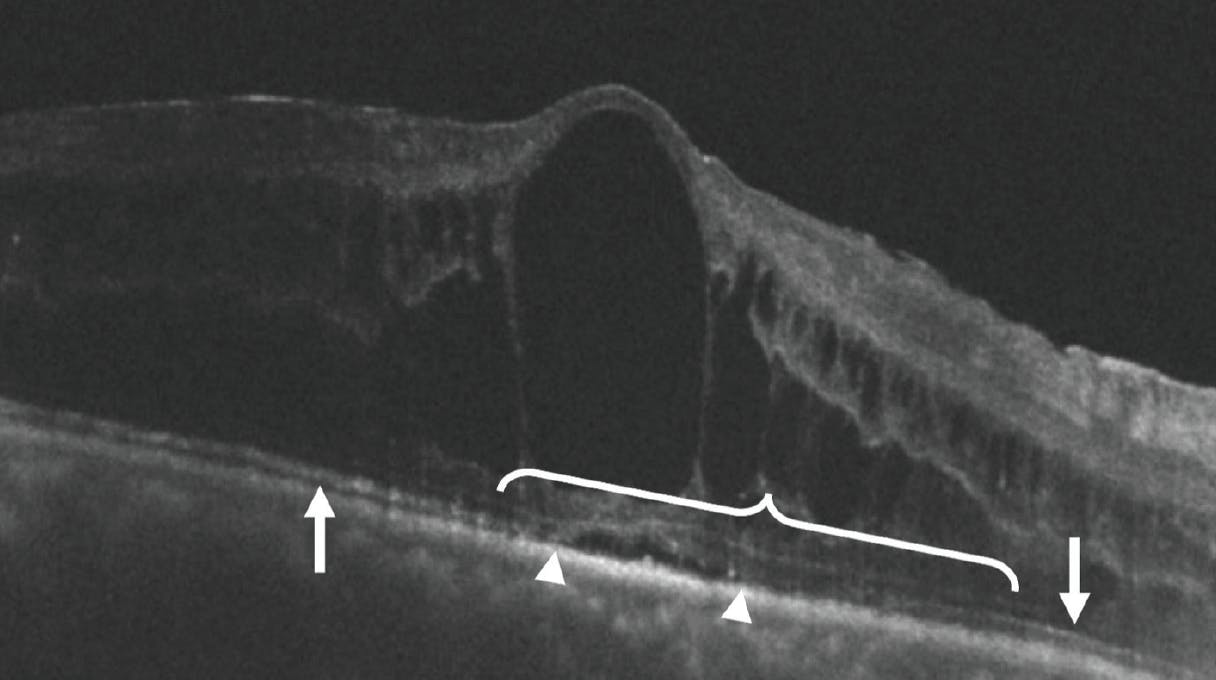

Loss of EZ integrity is associated with decreased visual acuity in a large number of retinal diseases (Figure 2). In UME, the degree of central subfield EZ disruption at baseline was associated with poorer baseline BCVA and poorer response to treatment in the pooled AZALEA/PEACHTREE trial UME cohort, although it may account for less than 30% of the total variation in BCVA, on average.5,11 A smaller study by Grewal et al analyzed 56 eyes from the VISUAL-1 trial of UME and found EZ integrity on OCT to be weakly associated with BCVA when averaged across all visits.19 Finally, degree of EZ disruption has been associated with intensity of corticosteroid therapy required to treat UME.20 These findings suggest that EZ analysis may be helpful in predicting clinical response to treatment; however, as with CST, EZ analysis alone is not sufficient for accurate prognostication in UME.

<p>Figure 2. The intact EZ (arrows) loses its integrity (bracket) within the area of UME. Note the mild serous retinal detachment (between arrow heads) causing significant EZ disruption. Overlying large central cystoid spaces and diffuse ME are also seen.</p>

Figure 2. The intact EZ (arrows) loses its integrity (bracket) within the area of UME. Note the mild serous retinal detachment (between arrow heads) causing significant EZ disruption. Overlying large central cystoid spaces and diffuse ME are also seen.